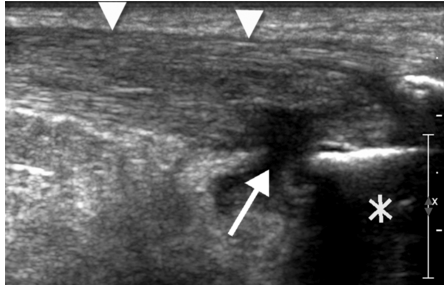

“Common tendon abnormalities include tendinopathy and tendon tears, which impose a substantial cost to society in the United States and abroad. According to the American Public Health Association, tendon disorders account for approximately $850 billion per year in health care costs and indirect lost wage expenditures.4 Accurate and timely diagnosis of musculoskeletal tendon injuries is critical to ensure proper treatment and thus minimize societal costs. Magnetic resonance imaging (MRI) has been the imaging standard for musculoskeletal injuries. However, MRI is costly and overused.5 Improvements in ultrasound technology have made sonography a rapidly growing imaging alternative and complementary tool to MRI for the diagnosis of common tendon injuries.6…..The most defining advantage of sonography over MRI is its real-time imaging capability, which allows for dynamic evaluation of the tendon using a variety of stress maneuvers.16,17 For example, in the neutral position, the long head of the biceps tendon may lie normally in the bicipital groove (Figure 3), only to dislocate medially once the arm, with elbow flexed, is externally rotated (Figure 4). In addition to tendon subluxation, other tendon abnormalities diagnosed dynamically include tendon snapping, friction between two structures such as in shoulder impingement,18 and increasing conspicuity of tendon tears while stressing the tendon or with sonopalpation.17 Real-time dynamic sonographic evaluation provides this unique diagnostic ability using controlled movements.”

Read more in this article to learn about what it means and what happens when the tendon goes from looking like this:

..to looking like this:

or like this….

with plenty more examples of it, illustrating how awesome it is and why we should use bedside ultrasound to evaluate tendons more.